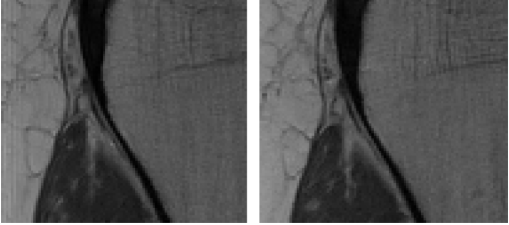

Fig. 2: Results on Denoising (Top row) and Super-Resolution (Bottom row) tasks using DiffPIR. We demonstrate perceptually comparable performance of our diverse prior in both patch-based (DiffPIRfull{}_{\text{full}}) and patch-based DiffPIRpatch{}_{\text{patch}} training.

4.1 Patch-wise trained models offer comparable performance to whole image models

As seen in Table 1, we demonstrate that our patch-wise trained prior offers comparable performance to a model trained at full image size. Specifically, when our model trained with patch size 128×128128\times 128 are used in whole image mode for plug-and-play, their performance is comparable to our whole image trained model, although the later is still slightly better. This is illustrated further in Fig. 2. This highlights that patch-based training could be an effective alternative when medical image resolutions grow (for example, ultra high resolution CTs) to render whole image training memory-intensive or even infeasible.